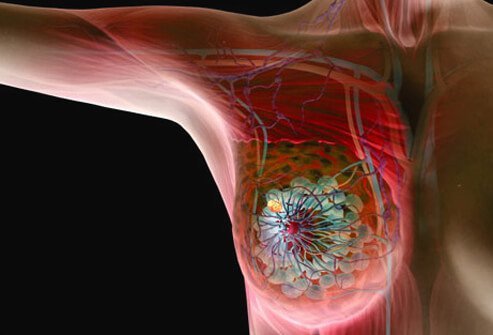

Invasive Ductal Carcinoma

Invasive (or infiltrating) ductal carcinoma (IDC) is the most common type of breast cancer. About 80% of all breast cancers are invasive ductal carcinomas. Invasive ductal carcinoma refers to cancer that has broken through the wall of the milk ducts and has invaded the breast tissues. Invasive ductal carcinoma can spread to the lymph nodes and possibly to other areas of the body.